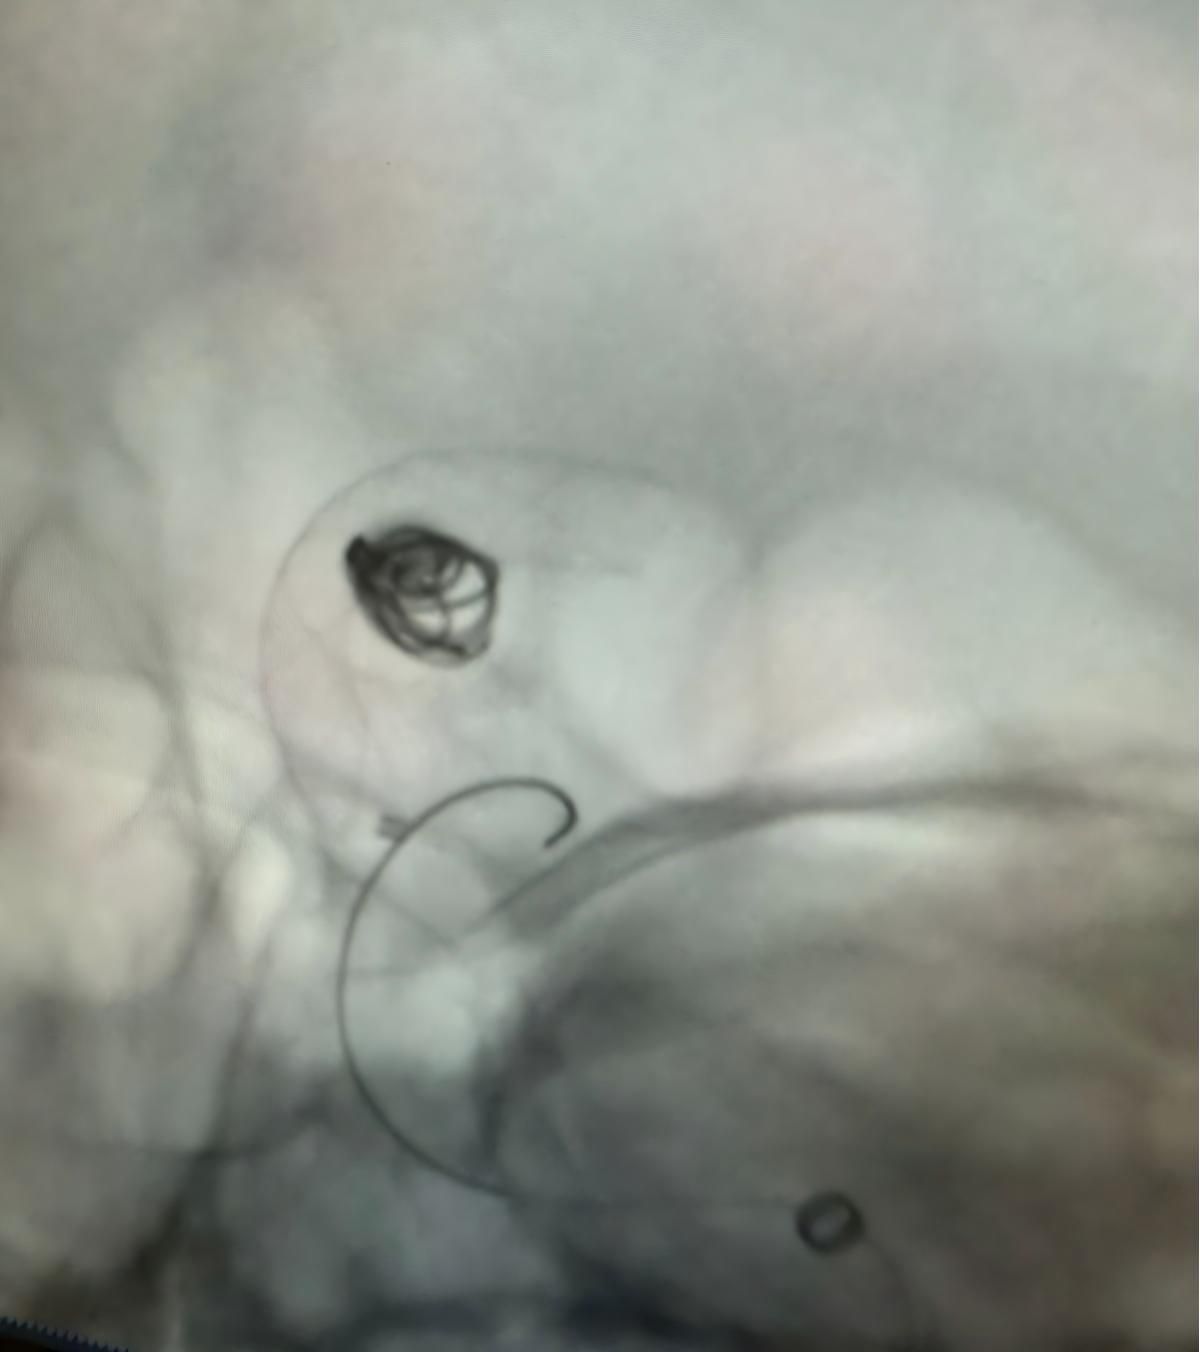

Мы рады поделиться недавней успешной процедурой в Клинике Альма Матер, Медельин, выполненной доктором Хорхе Мутисом.

Лечение использовалось Нува®Отвод потока (TJED-D 5,0-14), перденсатор®3D катушка и Frepass®Микрокатетер (TJMC18 Plus) для аневризмы задней сообщающихся артерий.

Доктор Мутис подчеркнул отличную видимость устройства и отметил, что извлечение было гладким. Он выразил большое удовлетворение в связи с окончательным результатом.